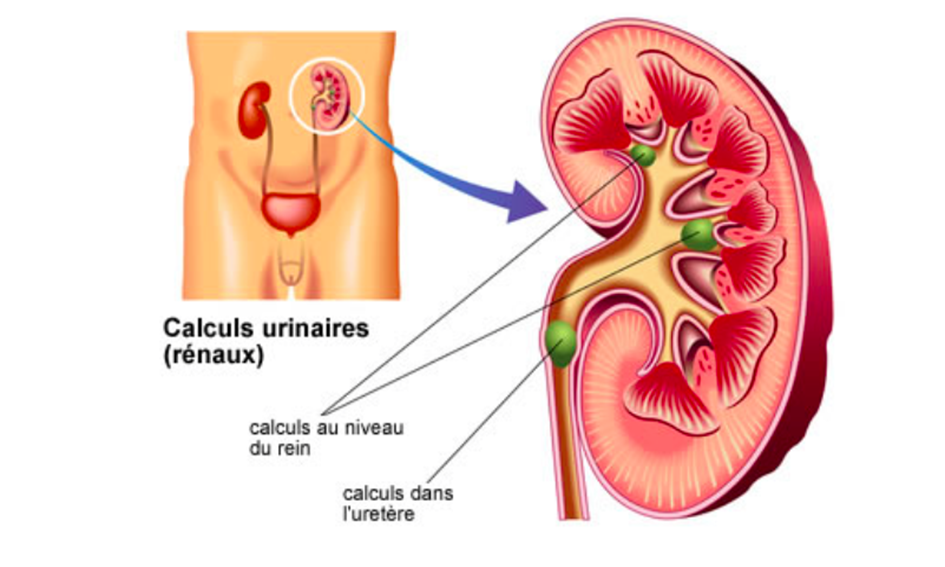

Définition des calculs urinaires et coliques néphrétique

Les calculs urinaires sont des concrétions (pierres) formées par l’accumulation de sels minéraux dans les reins ou les voies urinaires. Les calculs urinaires sont une maladie en constante augmentation dans les pays industrialisés. On compte qu’un habitant sur 10 présente un calcul urinaire. Ils sont 2 fois plus fréquents chez l’homme que chez la femme.

La colique néphrétique est une douleur intense provoquée par le passage d’un calcul qui bloque le flux d’urine dans l’uretère (le canal reliant le rein à la vessie), provoquant une mise en tension de la voie urinaire et du rein.

La colique néphrétique survient lorsqu’un calcul quitte le rein pour s’engager dans l’uretère et qu’il bloque le flux d’urine. La voie urinaire se met alors sous tension, et c’est cette tension qui provoque la douleur.

Il s’agit d’une douleur violente d’un seul côté, dans le dos, qui irradie en avant vers les organes génitaux externes. - Du sang dans les urines